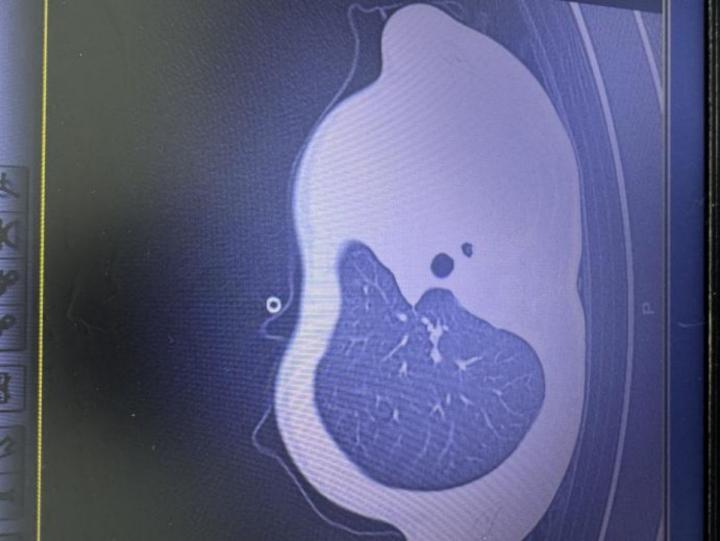

急診檢查結果讓醫護人員瞬間緊張:驗血顯示炎症指標大幅上升,胸片更發現左側肺葉幾乎“不工作了,影像學中變成大片白色,即通常所說的“白肺”意味着肺功能嚴重受損,孩子已經缺氧,隨時有窒息危險。

圖:影像顯示肺白了一半

“這是流感合併細菌感染引起的嚴重肺炎,同時發生了壞死性喉氣管支氣管炎,並有嚴重併發症,若不及時處理,幾小時就可能威脅生命!”楊醫生回憶。